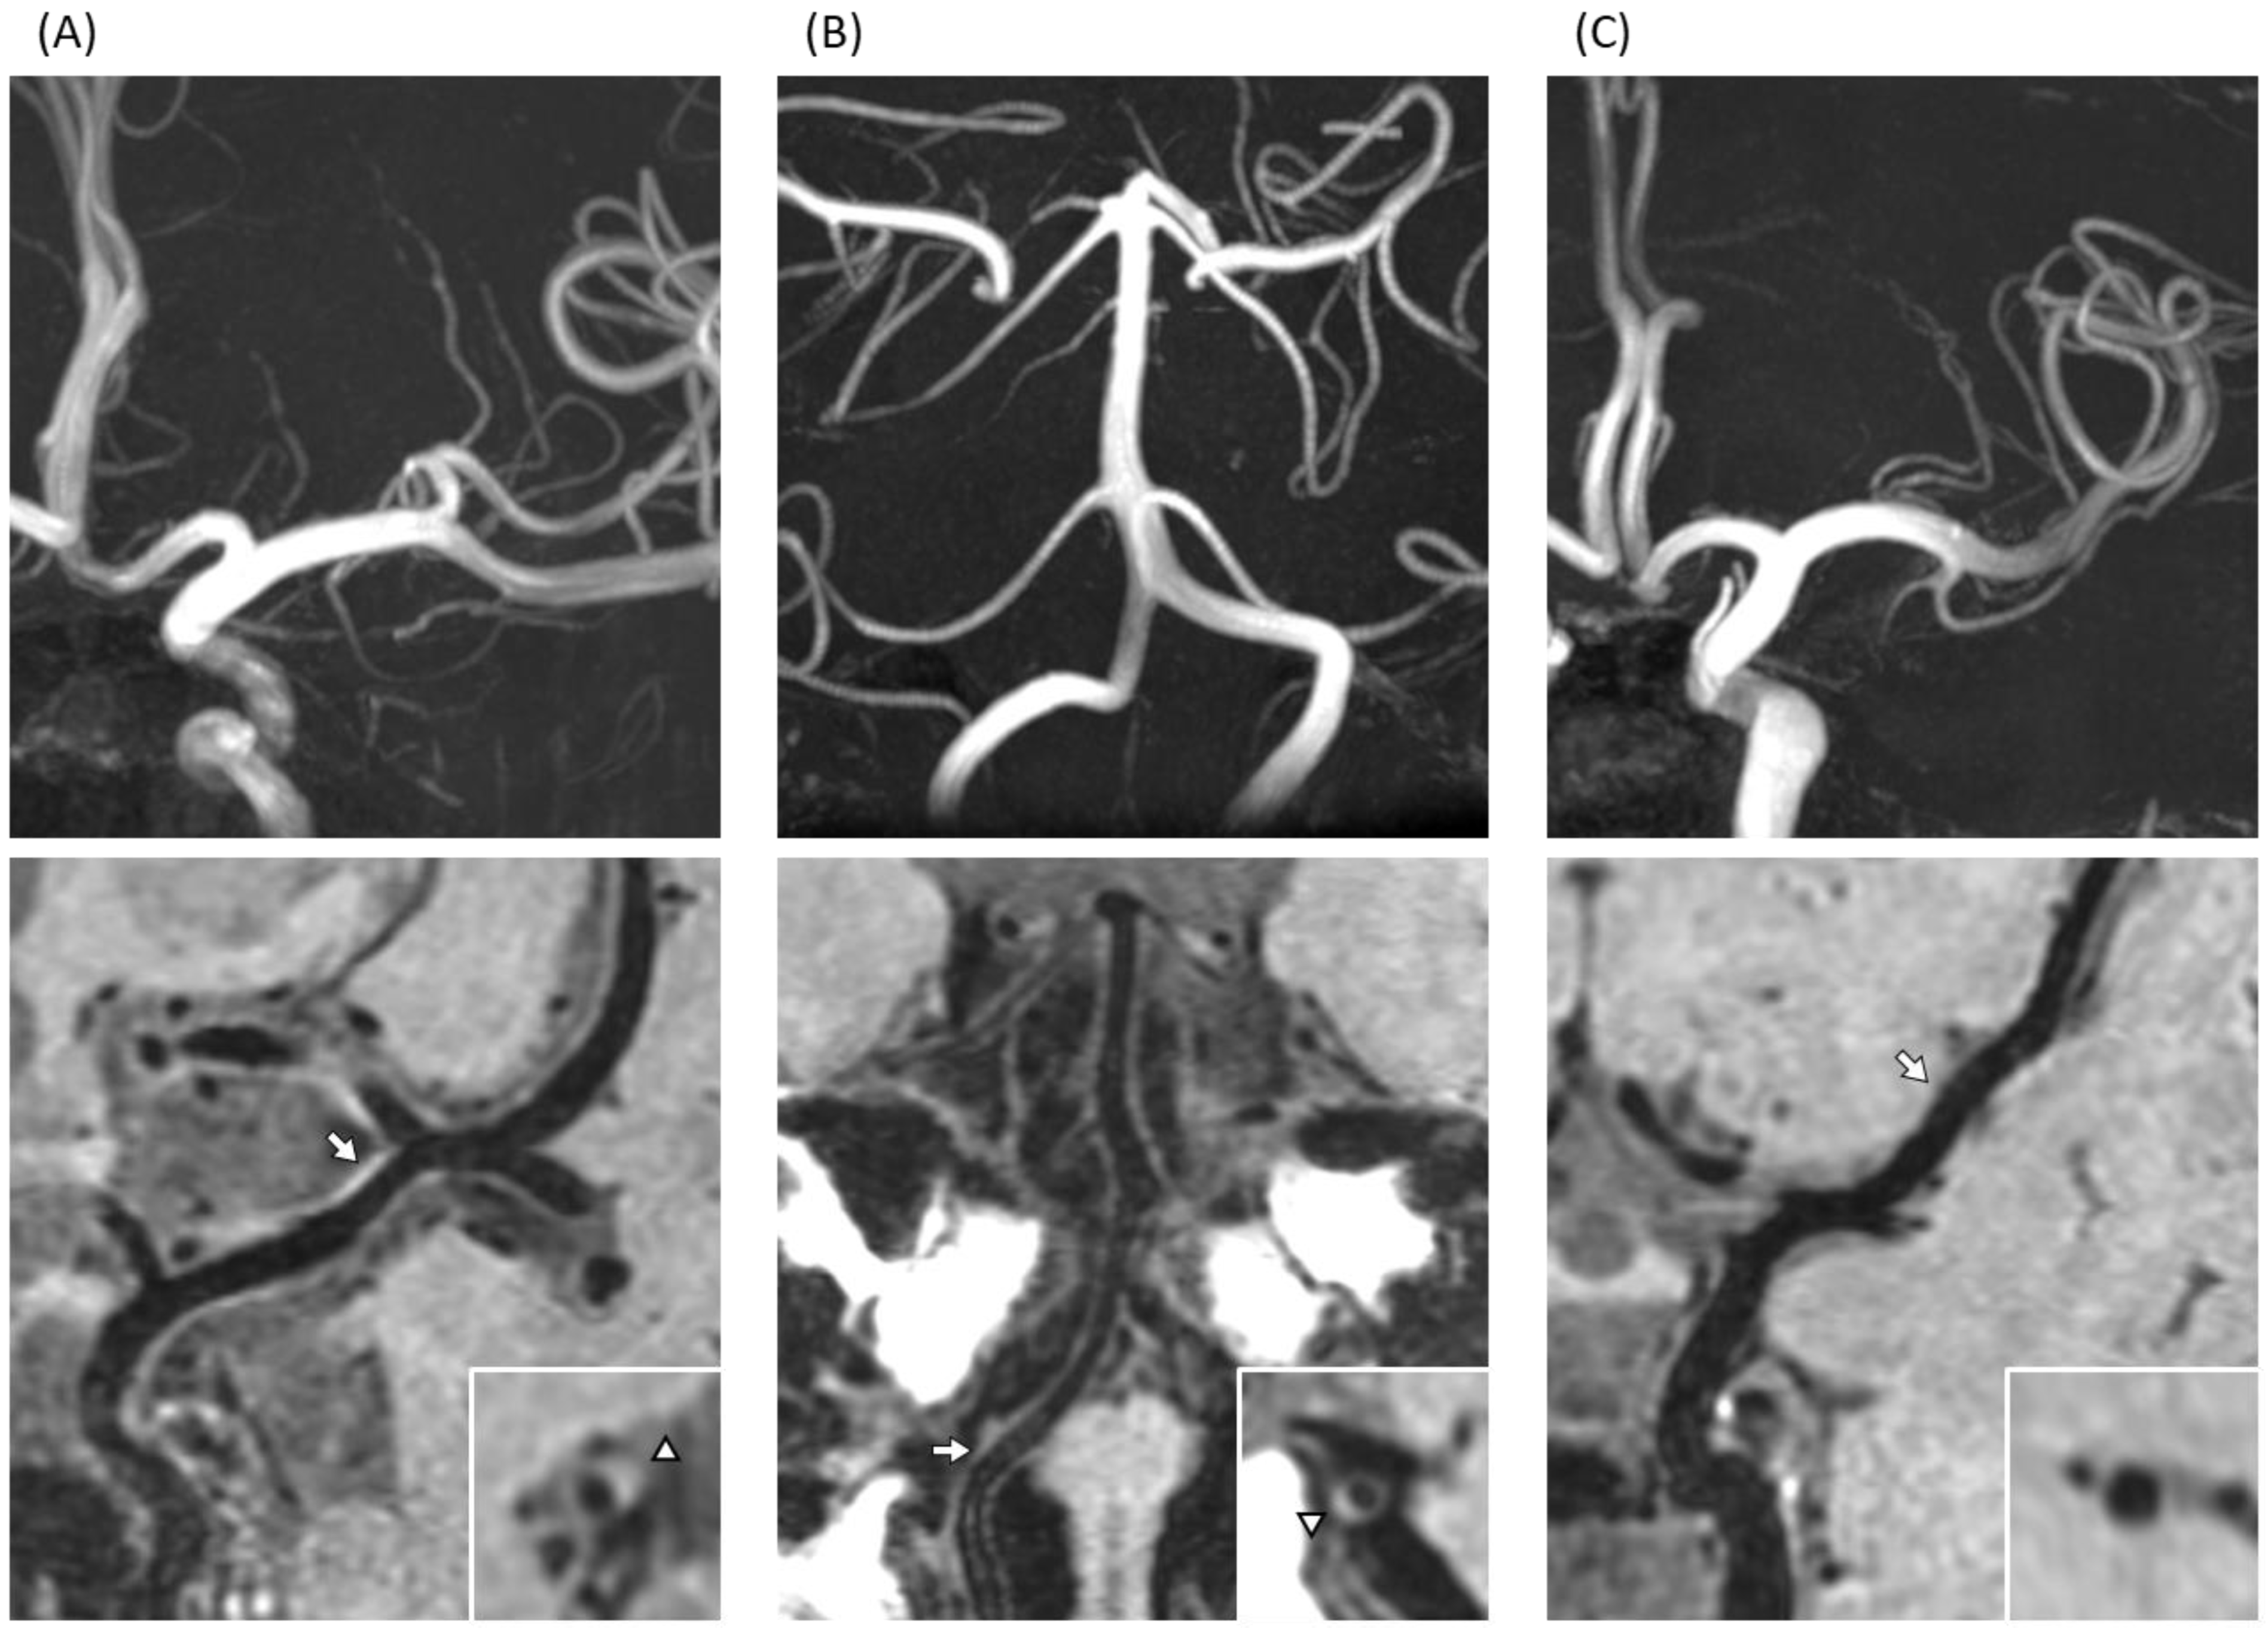

The conventional brain MRI scans revealed that the prevalence of lacunar infarction was significantly high in T2D compared with controls (n = 8 in T2D vs. n = 0 in control, p = 0.011). In contrast, no significant difference was found in the proportion of CMBs, DWMH, PVH, and brain atrophy between the two groups (Table 2). Next, apparent brain damage and large-vessel abnormalities were analyzed using 3D-VWI with 7TMRI (Figure 1). On high-resolution 3D-VWI, eccentric plaques were identified significantly more often in T2D patients than in controls. In both anterior and posterior circulation, the mean number of plaques in T2D patients was 2.23, whereas that of controls was 0.94, suggesting the prevalence of intracranial plaque to be significantly higher in the former (p < 0.01). Similarly, in the anterior circulation, the mean number of plaques in T2D patients was larger than in controls (1.52 vs. 0.51, p < 0.01), while no marked difference was detected in the posterior circulation (T2D 0.71 vs. controls 0.43, p = 0.069) (Table 3).

Figure 1.

T1-weighted three dimensional vessel wall imaging (3D-VWI) in type 2 diabetes mellitus (T2D) patients and a control. (A) A 59-year-old man with T2D had wall thickening at left MCA with high signal indicating atherosclerotic plaque, visualized by curved planar reformation (CPR) (arrow) and axial-sectional view (triangle). (B) A 56-year-old woman with T2D showed wall thickening at right VA with a high signal indicating atherosclerotic plaque, visualized by CPR (arrow) and axial-sectional view (triangle). (C) No plaques were detected in a 58-year-old woman from the control group, visualized by CPR (arrow) and axial-sectional view at indicated location by arrow.